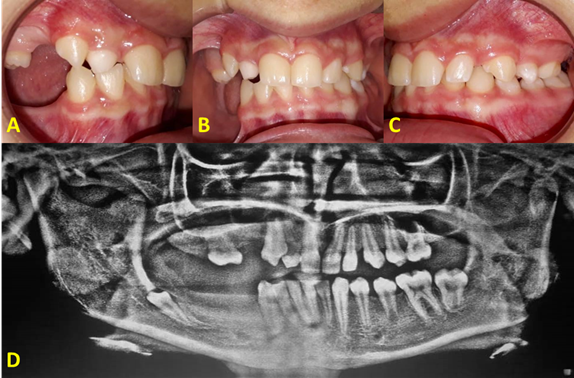

A routine odontogram was performed in the intraoral examination. Molars and premolars were missing in the posteroinferior area, as well as upper premolars on the left side (Fig. 2D and 2E); morphological alterations in teeth and persistence of primary teeth (Fig. 3A, 3B and 3C). In addition, the ridges were reduced in height and thickness; during palpation, the patient reported slight localized and short-lived pain in the right posteroinferior area. The periodontal examination showed good gingival health.

Fig. 3: A. (Agenesis and diminished ridges in sextants 1 and 6). B. (Intraoral asymmetry due to missing teeth) C. (Occlusal accommodation) D. (Current panoramic radiography).

Radiographic features

A panoramic radiography was taken and we observed the asymmetry of the mandibular bodies, slight maxillary sinus pneumatization, apparently normal nasal septum and turbinates. Temporary teeth were observed, as well as agenesis of permanent teeth, delay in apical maturation, delay in eruption chronology and a retained tooth (Fig. 3D).